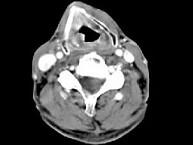

问题 男,63岁,咽喉部不适约一年,近2个月经常咳嗽,痰中带有血丝,CT如图所示,应诊断为 ( )

选项 A、声门上型喉癌 B、混合型喉癌 C、声门型喉癌 D、声门下型喉癌 E、梨状窝癌

答案 A